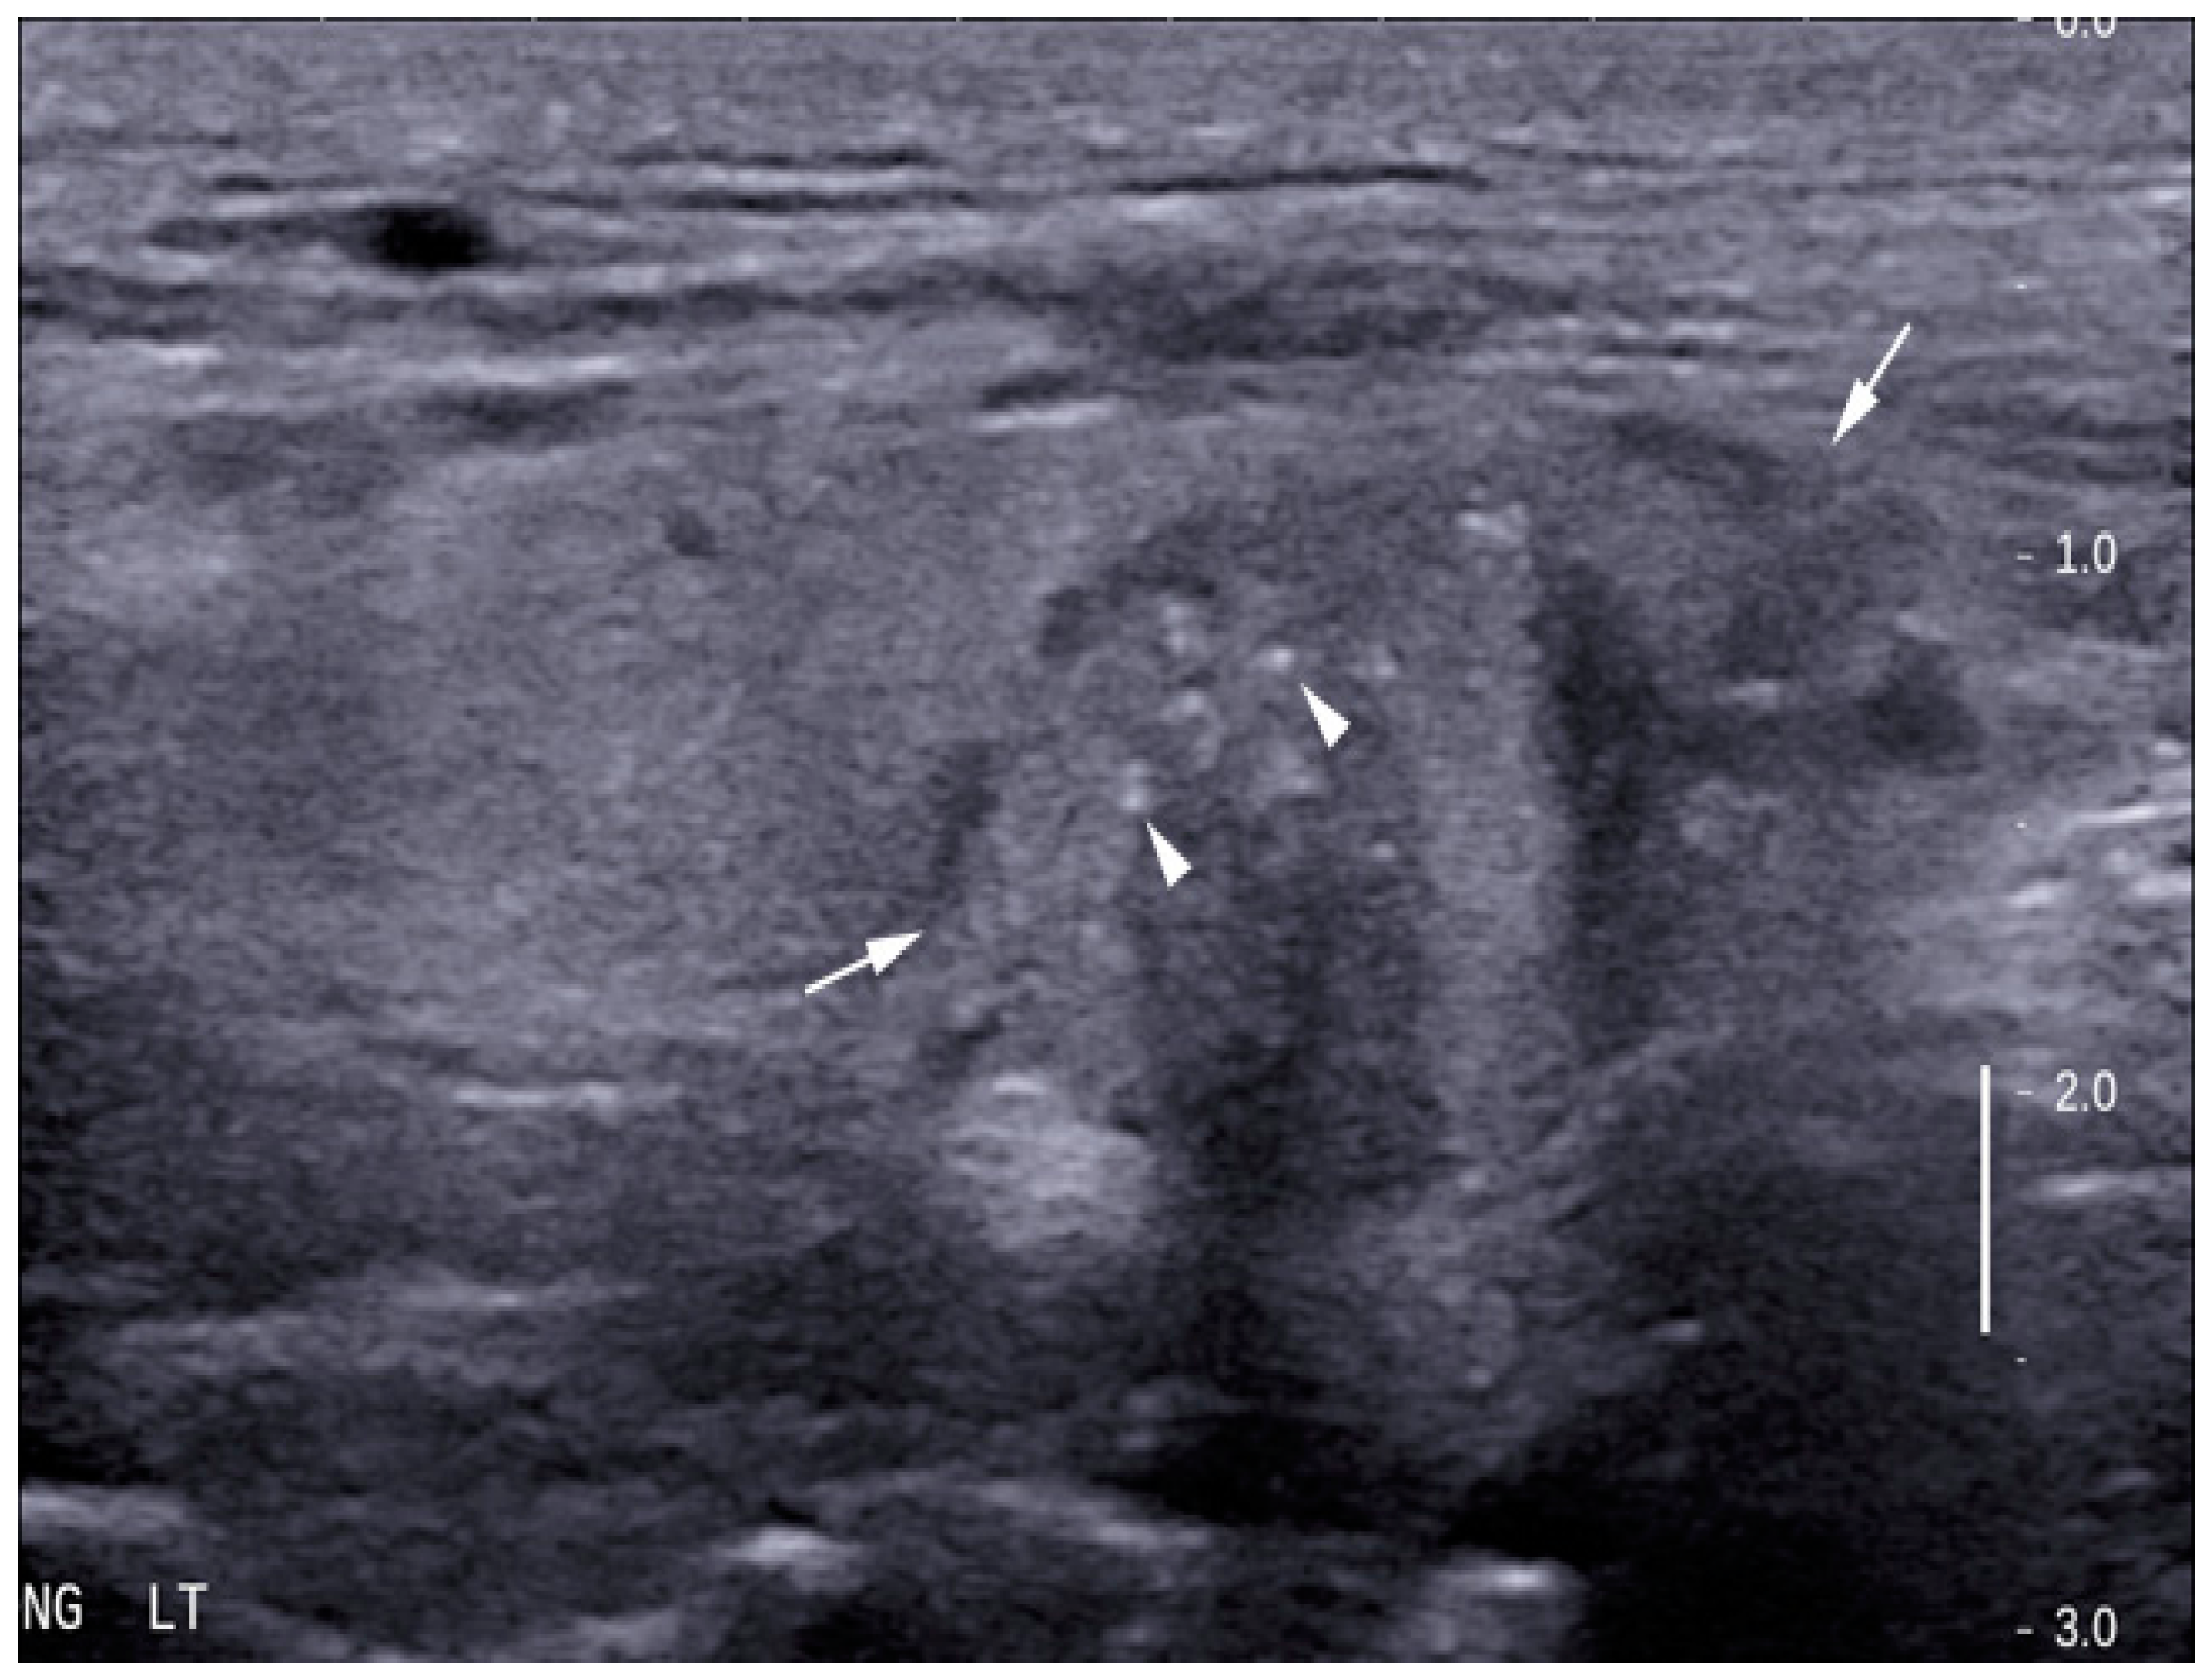

| Microcalcification | |||

| Yes | 6 (7.1%) | 21 (77.8%) | <0.05 |

| No | 78 (92.9%) | 6 (22.2%) | (0.12–0.49) |

| Tall/width ratio >1 | |||

| Yes | 11 (13.1%) | 16 (59.3%) | <0.05 |

| No | 73 (86.9%) | 11 (40.7%) | (0.29–0.74) |

| Hypoechogenicity | - | - | - |

| Yes | 28 (33.3%) | 25 (92.6%) | <0.05 |

| No | 56 (66.7%) | 2 (7.4%) | (0.42–0.71) |

| Irregular margins | |||

| Yes | 14 (16.7%) | 15 (55.6%) | <0.05 |

| No | 70 (83.3%) | 12 (44.4%) | (0.38–0.83) |